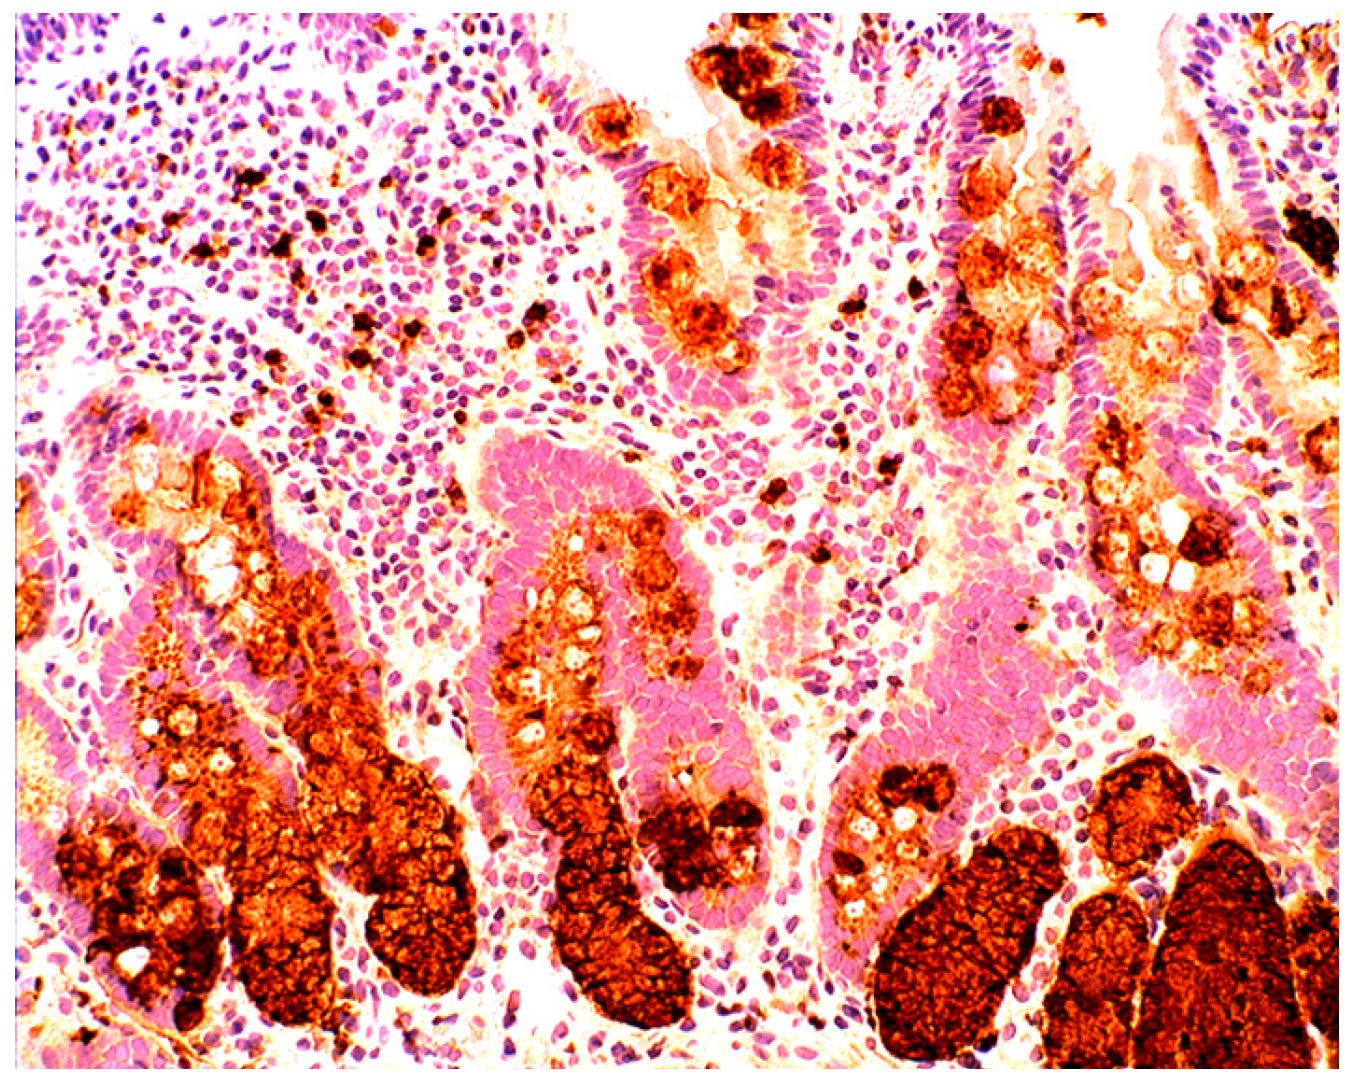

Increased lysozyme immunoreactivity was found In Barrett’s oesophagus; in the surface columnar epithelium, in the columnar epithelium of the pits of the glands (Figure 1), in goblet cells (Figure 2), as well as in Paneth cells in cases with intestinal metaplasia [24].

Barrett’s mucosa (intestinal phenotype) showing lysozyme up-regulation, particularly in the luminal epithelial border and in goblet cells (lysozyme immunostain, ×40).

When compared to controls, lysozyme was up-regulated in all three Barrett’s mucosal phenotypes [24]. In some goblet cells, lysozyme was slightly expressed. This phenomenon might be due to a prior goblet cells-discharge of lysozyme-rich intracellular mucus into the lumen (Figure 3). Lysozyme was not expressed in parietal (oxyntic) cells, neither in Barrett’s oesophagus (Figure 4), nor in controls [24].

Close-up view of Barrett’s mucosa of intestinal phenotype, showing faintly stained goblet cells and at arrow, marked lysozyme expression in the secreted mucus, in the lumen of the gland (lysozyme immunostain, ×40).